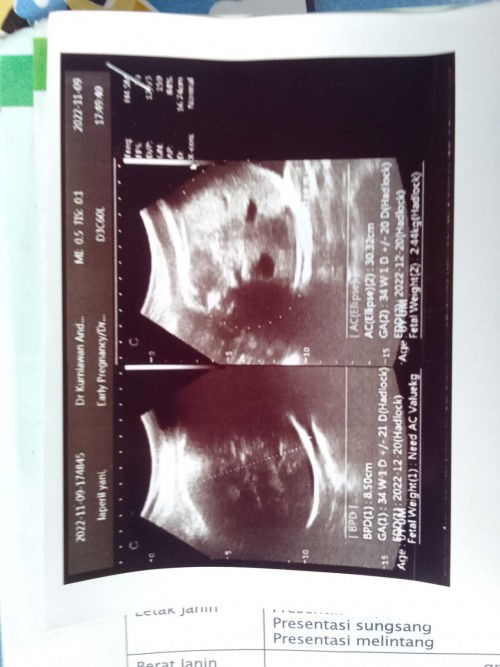

BINGUNG Hasil uSG

Cara baca hasil uSG ini gimana si Bunn. Tolong dong bagi yang tau. HPL aku kena tgl berapa yaaa??

hpl kalo gak salah yg tulisan EDD Bun.